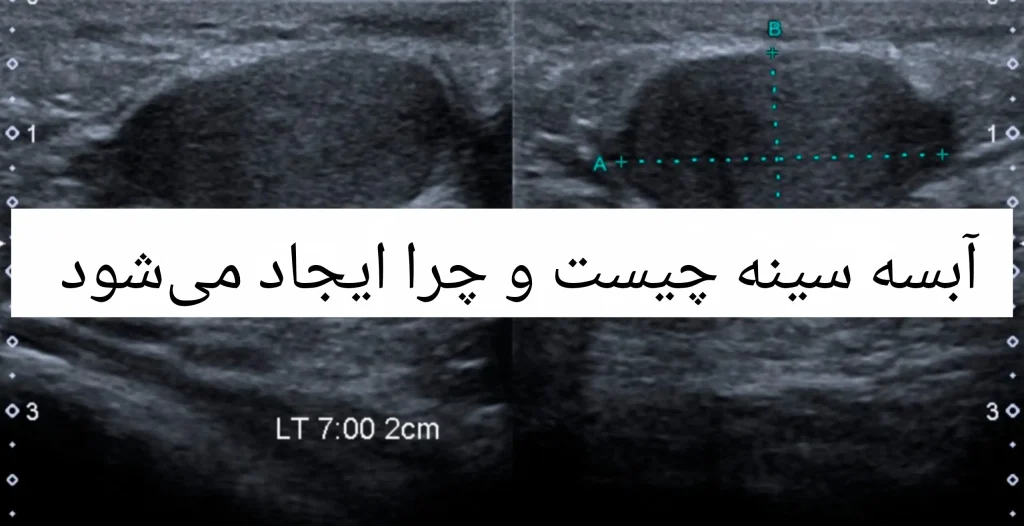

مراحل تشخیص آبسه سینه

تشخیص آبسه معمولاً از طریق معاینه بالینی و تصویربرداری انجام میشود:

- معاینه فیزیکی

پزشک با لمس ناحیه متورم، حساسیت و گرمی پوست را بررسی میکند. همچنین ممکن است بررسی شود که آیا توده قابل حرکت است یا به بافت عمیق متصل است. - سونوگرافی پستان

سونوگرافی سینه رایجترین روش برای تشخیص آبسه است و میتواند موقعیت، اندازه و عمق آبسه را نشان دهد. این روش بدون تابش اشعه است و برای مادران شیرده مناسب است. - نمونهگیری و کشت چرک